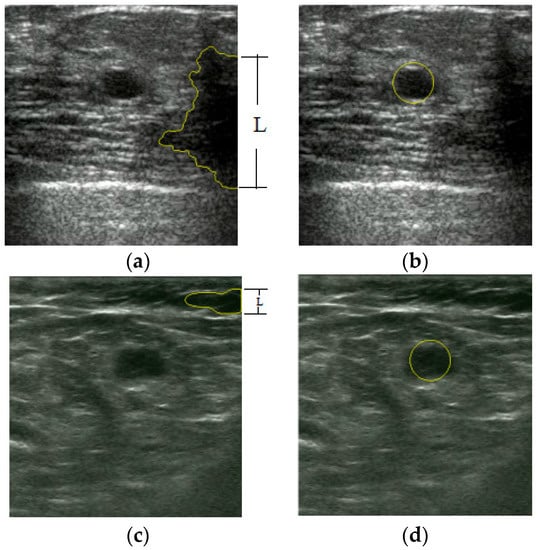

An Automatic Localization Algorithm for Ultrasound Breast Tumors Based on Human Visual Mechanism

Xie, Y.; Chen, K.; Lin, J. An Automatic Localization Algorithm for Ultrasound Breast Tumors Based on Human Visual Mechanism. Sensors 2017, 17, 1101. https://doi.org/10.3390/s17051101